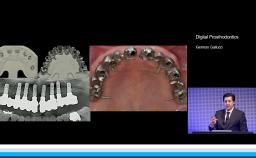

My ITI - German Gallucci

German Gallucci